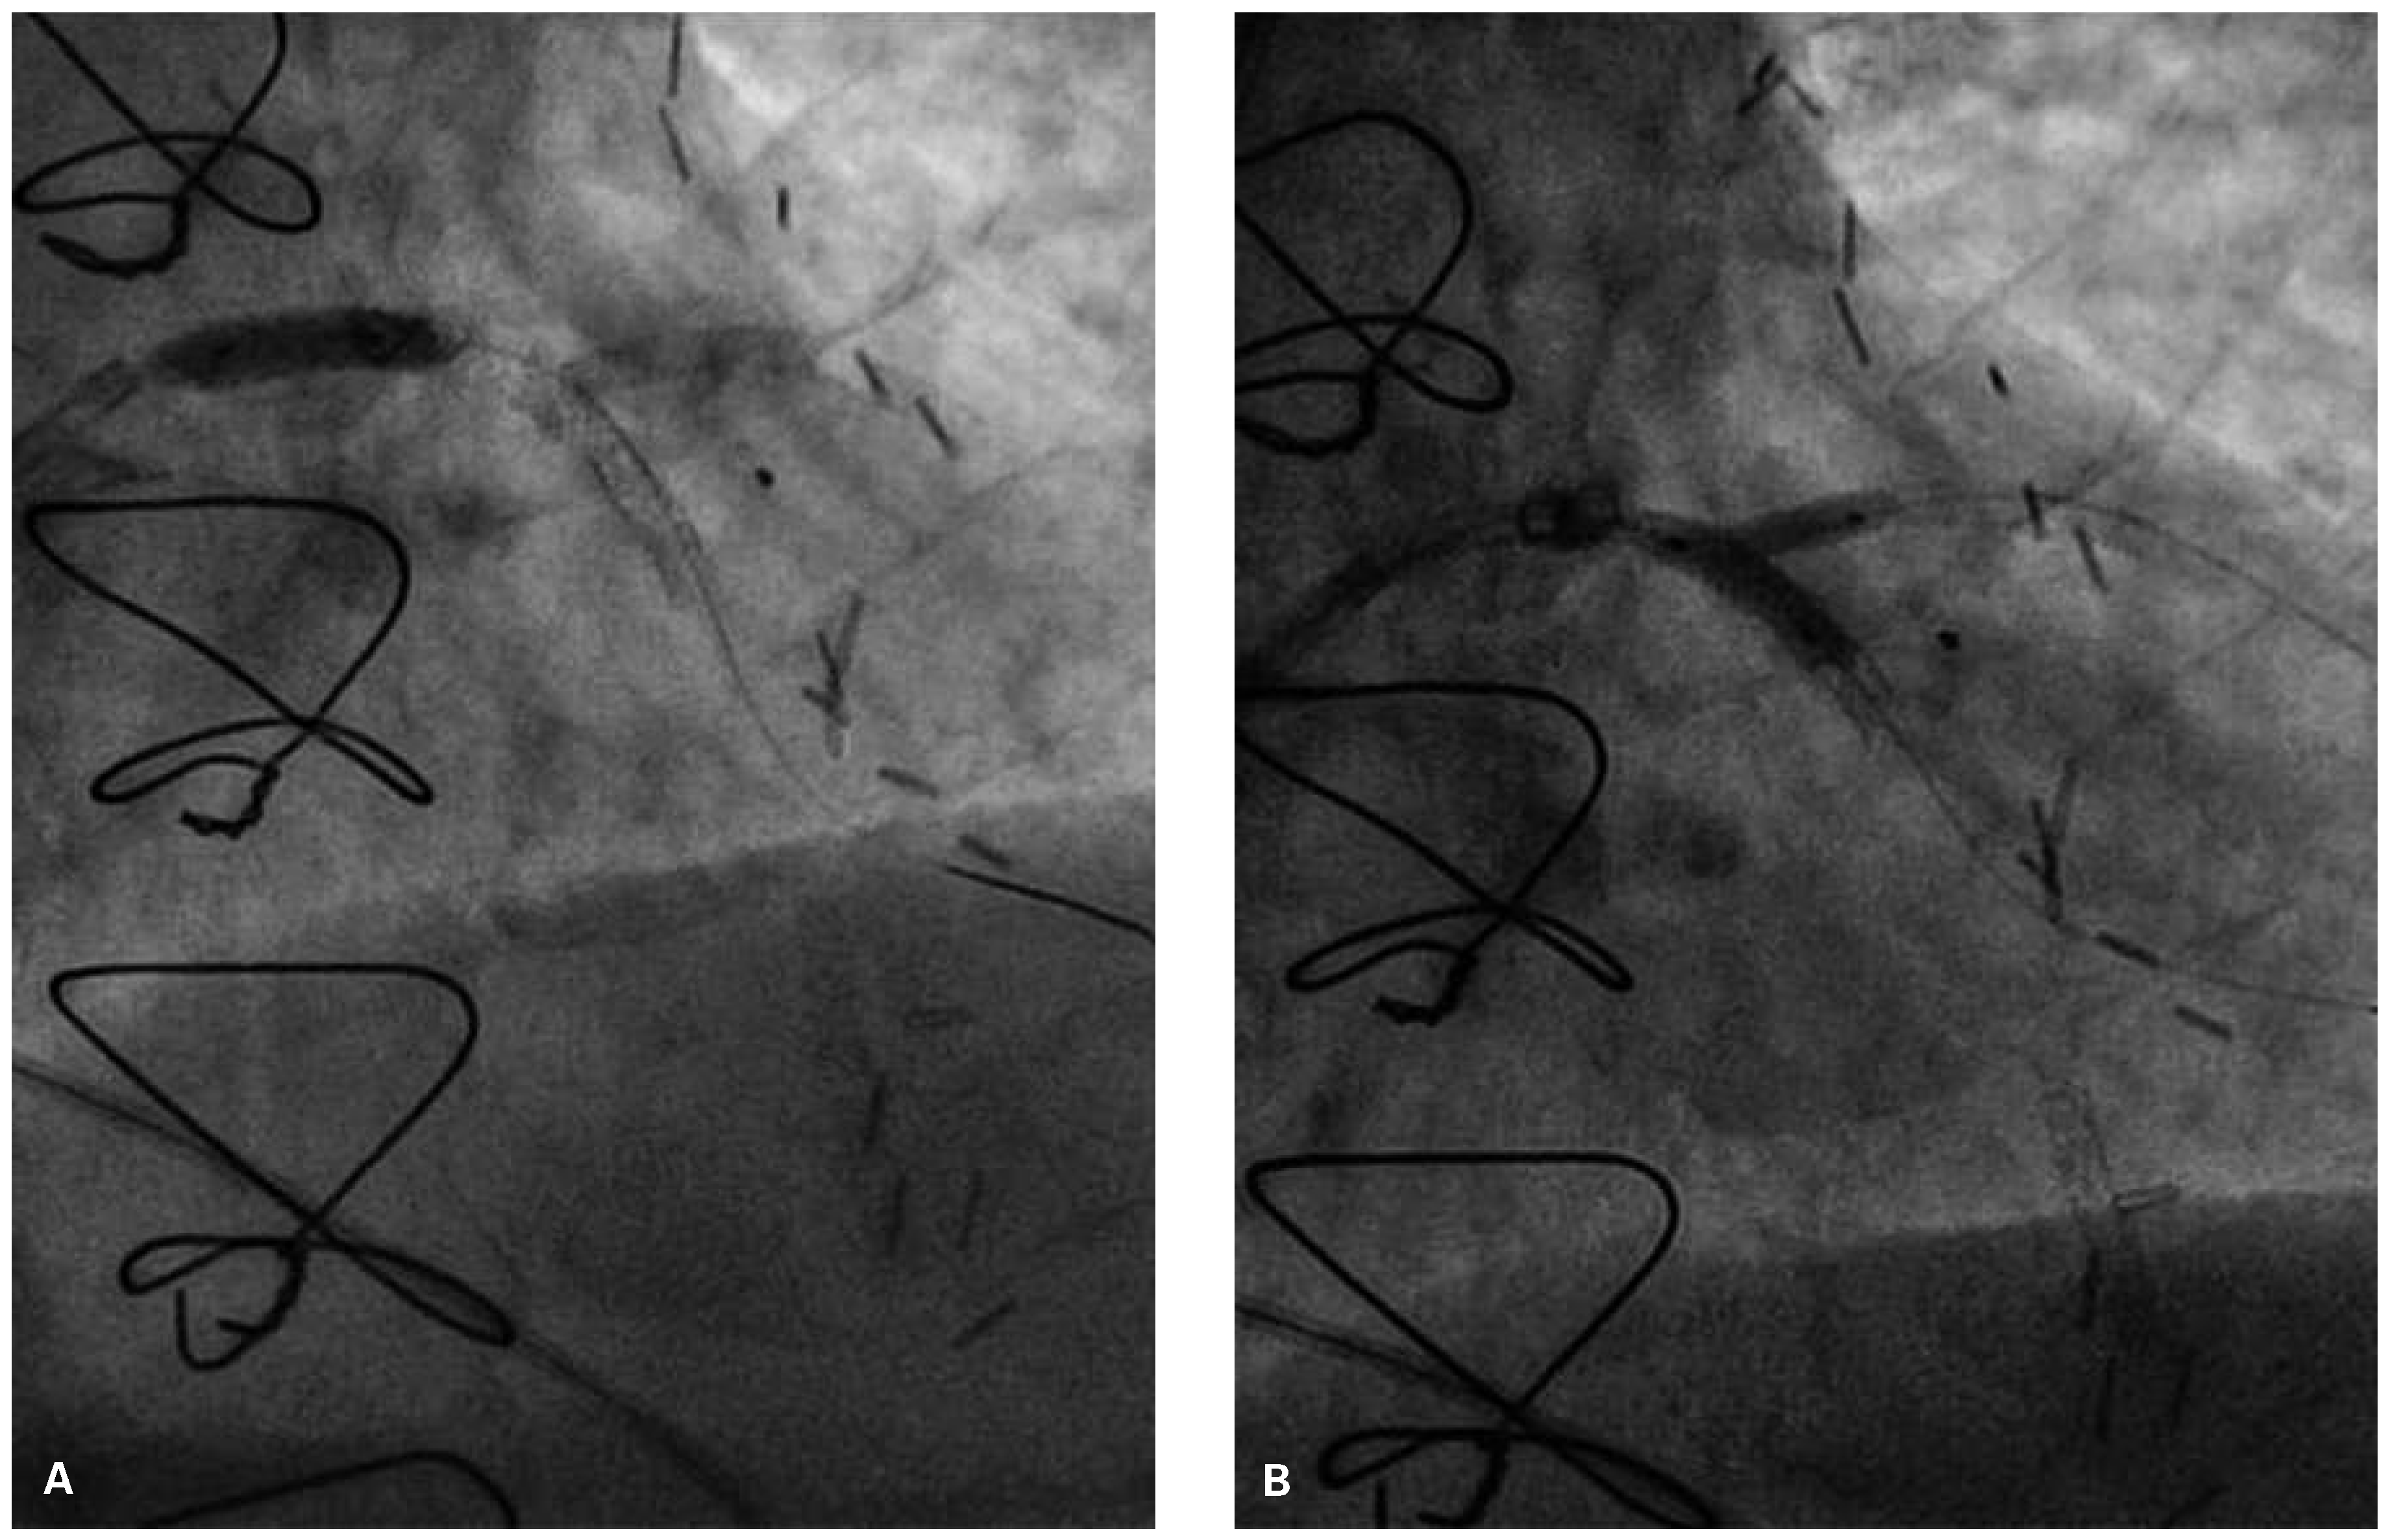

Following RA, both LAD and diagonal were wired with ease using separate Runthrough (Terumo, Japan) wires. Predilatation of both bifurcation limbs was undertaken using 1.5 × 15 mm Trek (Abbott) and 2.0 × 10 mm Sapphire (Orbus-Neich, Hong Kong, China) semicompliant balloons, which both expanded well at nominal pressure. Intending to perform an elective T-stent strategy, a 2.25 × 28 mm Promus Premier DES was deployed at 18 Atm in the diagonal branch, landing proximally at the ostium of this vessel (Figure 3). After removal of the diagonal wire, a 3 × 38 Promus Premier stent (Boston Scientific) was sited from the origin of the LMS across the first diagonal and deployed at 18 Atm (Figure 4). The diagonal branch was then rewired with the runthrough wire. A kissing inflation was performed at 12 Atm using a 3.5 × 12 Quantum (Boston Scientific) and 2.5 × 12 Sapphire noncompliant (NC) balloons in LAD and diagonal, respectively (Figure 5A). The proximal LAD and LMS were then optimised using the 3.5 Quantum NC (LAD) and a Hiryu (Terumo) 4 × 10 NC (LMS) balloons at 22 and 18 Atm, respectively (Figure 5B). The final angiographic result was excellent (Figure 6). Intravascular ultrasound of the LMS was not undertaken as angiographically the LMS stent already appeared completely expanded and oversized. We opted not to intervene in the ostial left Cx in order to best preserve the geometry of the LMS stent.

Figure 5. LAO 30°, cranial 30° view. (A) Kissing inflation with a 3.5 × 12 Quantum NC and 2.5 × 12 Sapphire NC balloons in LAD and diagonal, respectively; (B) Hiryu (Terumo) 4 × 10 NC deployed in the LMS.